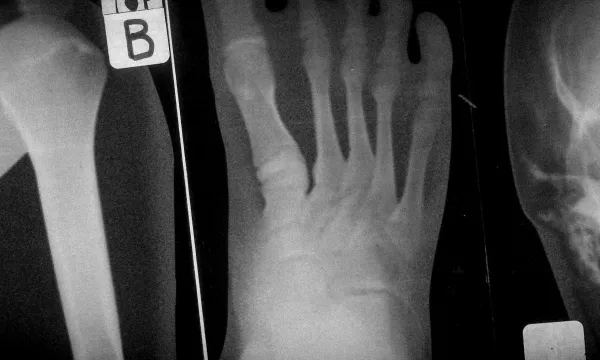

An exciting workshop where students learn more about the insides and outsides of their own amazing bodies, use digital microscopes, diagnose broken bones with real x-rays, and turn their classmates inside out!

Examine real x-rays and identify the bones of the human skeleton (including broken and fractured bones - KS2).

Identify and name the bones of the human skeleton (including where bones are broken - KS2).